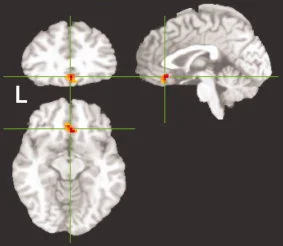

2009年,美国国立神经疾病与中风研究所的研究团队在《Human Brain Mapping》上发表了一项开创性的fMRI研究。他们让18名健康受试者观看四种不同的视频:打哈欠、张嘴(类似哈欠但没有情感成分)、咳嗽和中性表情。

研究发现,当受试者观看打哈欠视频时,腹内侧前额叶皮层(vmPFC)显著激活,这是唯一在哈欠条件下特异性激活的脑区。这个区域在坐标空间中的位置约为 $x=1.5$,$y=25.5$,$z=-9.5$(Talairach坐标系),最大Z值达到3.95。

腹内侧前额叶皮层是什么?它是大脑中参与情感处理、决策制定和社会认知的关键区域。研究发现,这个区域的损伤会导致共情能力下降——患者难以理解他人的情感状态。这提示传染性哈欠可能与社会认知和共情能力有关。

值得注意的是,研究还发现了一个反直觉的结果:镜像神经元系统并不是哈欠传染的核心。虽然观看哈欠视频时,镜像神经元相关的脑区(如腹侧运动前皮层)也有激活,但这些区域在观看"张嘴"视频时同样激活。真正的差异只出现在腹内侧前额叶皮层。

图片来源: PMC/NIH - 显示腹内侧前额叶皮层在观看哈欠视频时的特异性激活